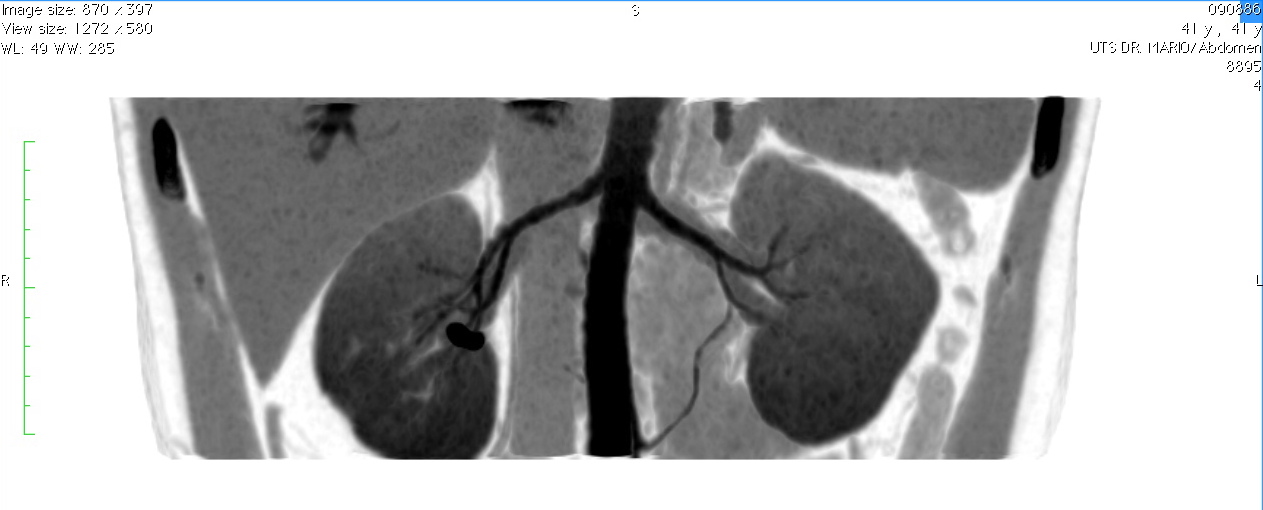

КТ ангио почек. 3D MIP

Артериальная мальформация правой почки. Некая аномальная артерия левой почки